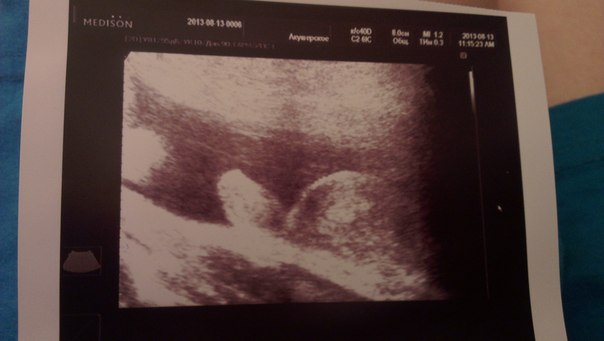

пальчики считали,пяточки смотрели,сердечко четырехкамерное,все шикарно врач сказала,весим мы уже 2100 гр! Иииии,у нас сыночек,как и предположили в 12 недель!

после такой фотки сомнений не осталось